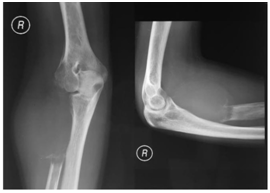

We found three subjects with GCT of the elbow (Table 1). Two subjects were male with the age of 30 and 31 years old, other subject was a 19 years old female. The patients came to the outpatient clinic with the symptoms of pain. On the physical examination we found deformity enlarging mass, and limited range of movement (ROM) (Figure 2). Anteroposterior and lateral radiographic findings were osteolytic mass at proximal radius that expanded to metaphyseal and diaphyseal region. The MRI finding was high intense mass (Figure 3) (Figure 4).

Figure 3 Radiographic findings show osteolytic mass at proximal radius that expanded to metaphyseal and diaphyseal region.